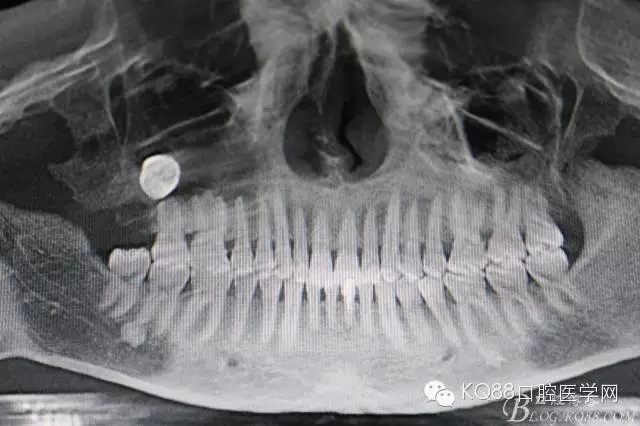

圖2.術前做全景片影像檢查:18頰舌向高位阻生,牙冠位于17牙根的正上方,懷疑18位于上頜竇內(nèi)。